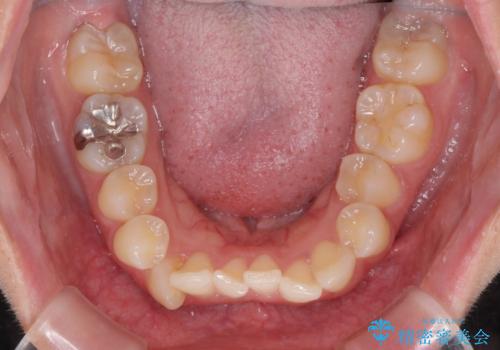

八重歯の抜歯矯正 補助装置とワイヤーを併用したインビザライン矯正治療

- 八重歯と上顎正中のズレを気にして来院された患者様です。

インビザラインによる矯正治療を希望されたため、八重歯改善のための抜歯矯正部分や上顎正中の大幅に位置移動は、補助装置やワイヤー矯正を併用し、その後はインビザラインにて行うこととしました。

ワイヤー矯正単体の方が期間や仕上がりは優位であるとご説明しましたが、インビザラインでの治療を希望されたため、補助装置併用の矯正治療を行うこととしました。

骨格的に下顎が左側に変位していたため、上下正中を合わせることは困難であることは分かっていましたが、可能な限り合わせることができました。

骨格的なズレがあると仕上げの段階で奥歯の咬み合わせが不安定となるため、予定よりやや長期間となりました。